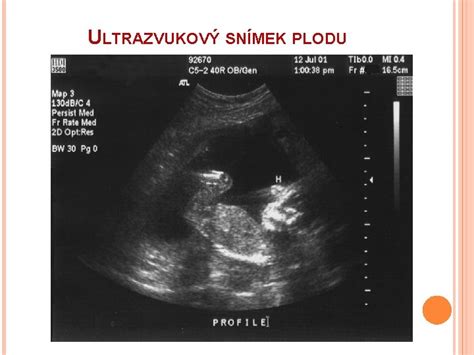

V rámci sledovania tehotenstva sa vykonávajú aj ultrazvukové vyšetrenia. Zdravotná poisťovňa hradí tehotným pacientkam 3 USG vyšetrenia: v 10., 20. a 30. týždni tehotenstva. Tieto vyšetrenia sú zamerané na vyhľadávanie vrodených vývojových chýb plodu, posúdenie jeho veľkosti a uloženia v maternici. Špeciálne USG vyšetrenia v tehotnosti sa vykonávajú na špecializovaných pracoviskách. CTG záznam na monitorovanie stavu dieťaťa sa vykonáva v týždenných intervaloch od 36. týždňa tehotenstva.